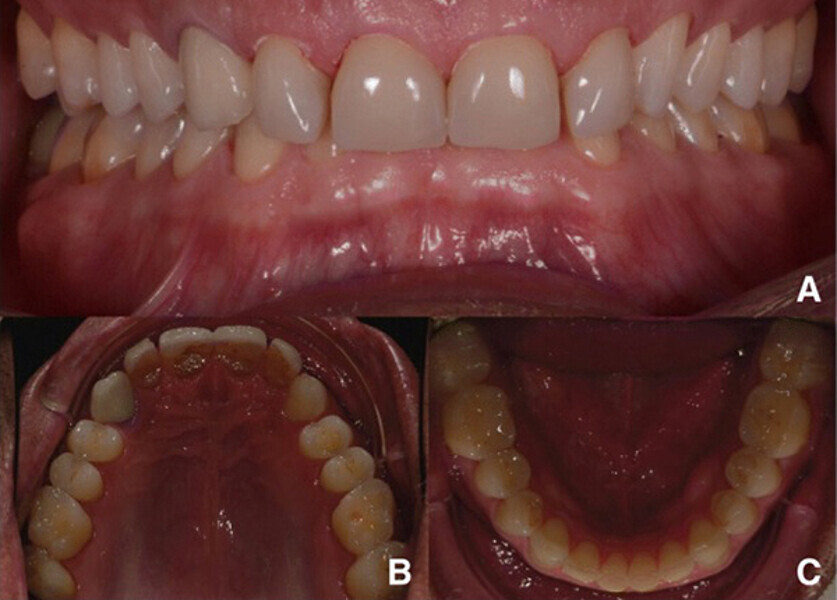

Fig. 1. Fotografías intraorales iniciales, vista frontal (A), vista oclusal del maxilar (B) y vista oclusal de la mandíbula (C).